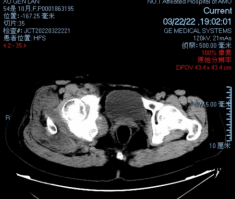

术前影像

穿刺活检提示骨盆软骨肉瘤

日前,安医大一附院骨病骨肿瘤外科胡勇教授团队成功完成一例复杂骨盆Ⅰ+Ⅱ+Ⅲ+Ⅳ区肿瘤切除与3D打印组配式半骨盆假体重建手术。患者为女性,53岁,下腰痛半年余,右侧臀部膨隆,右侧下肢轻度浮肿。右侧髂棘髂窝及臀部可触及巨大肿物,压痛明显,右髋外展前屈活动受限,右侧大腿感觉麻木,右足感觉运动正常。骨盆肿瘤切除重建是骨科专业中难度极大、风险极高的手术。骨盆肿瘤约占原发骨肿瘤的3%~4%,其中以软骨系统肿瘤最为多见,其次为骨巨细胞瘤、成骨肉瘤等,儿童尤文肉瘤亦好发于骨盆。

骨盆恶性肿瘤常潜在发展,由于骨盆位置较深,肿瘤早期很难发现,从第一次出现症状到诊断明确有时需要很长时间,当出现临床症状时,肿瘤体积已较大,因而手术切除相当困难。骨盆肿瘤血供丰富,手术出血多、难度大。另外,骨盆形态特殊,解剖复杂,切除肿瘤的同时,需要重建骨盆结构和肢体功能,技术要求高。